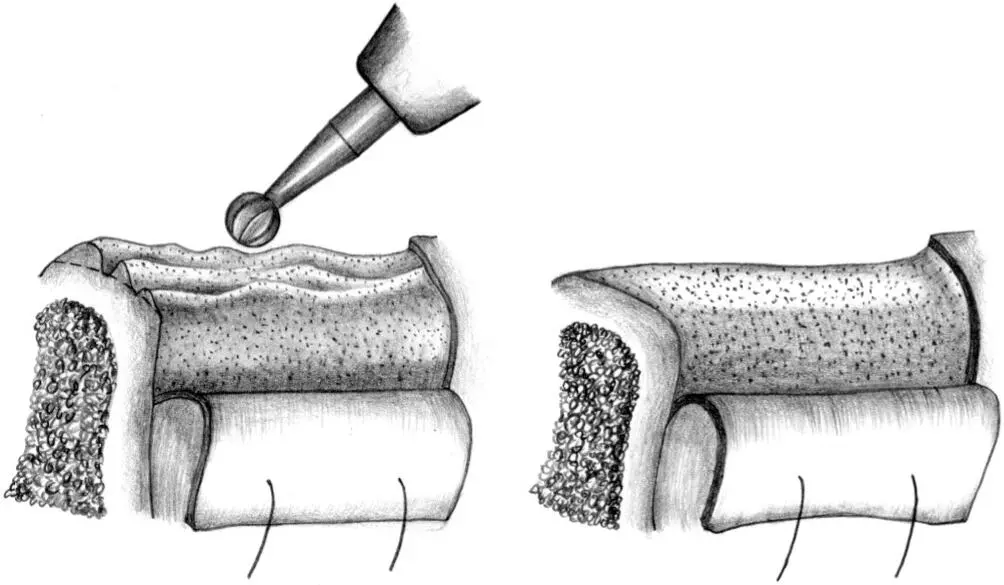

Fig 1-3Correction of the position and axis of the implant site preparation.

Fig 1-3a The preparation of the implant site begins with the use of the nos. 1 and 2 round burs to mark the position of the implant site.

Figs 1-3b and 1-3c Any required changes to the marking made with the first round bur can be accomplished with the no. 2 round bur, as shown in this occlusal view. These initial steps for the preparation of the implant site ensure the correct implant position orofacially and mesiodistally.